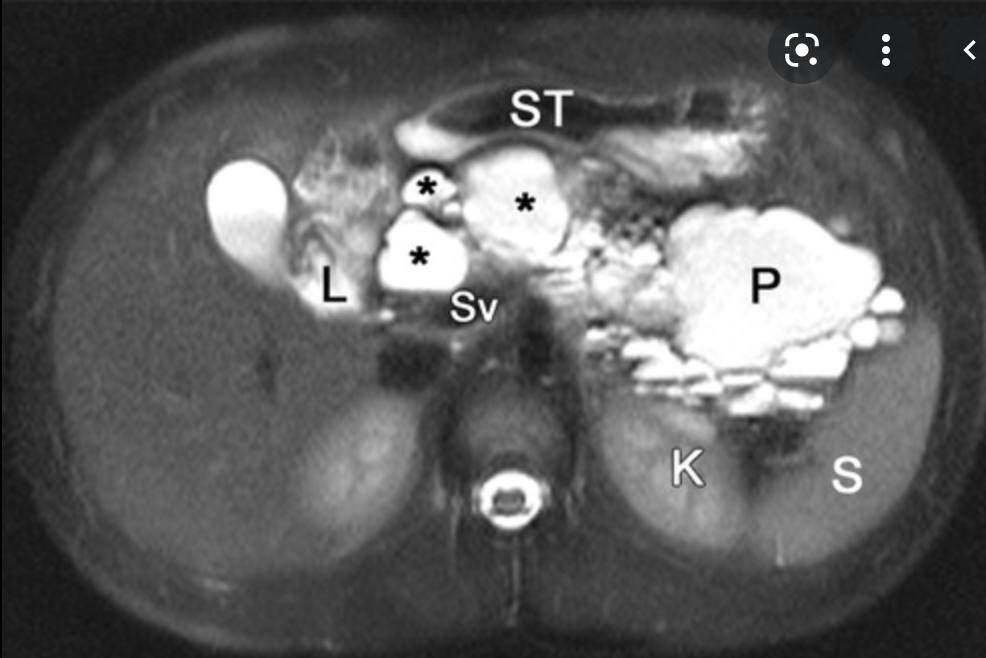

Single phase CT scan (multiphase scans not performed due to age of patient) demonstrates a diffusely enlarged pancreas with a “halo” like rim of hypoattenuating tissue which is smoothly marginated. Minimal peripancreatic fat stranding.

Associated splenic vein thrombosis, splenomegaly and cavernous transformation of the portal vein.